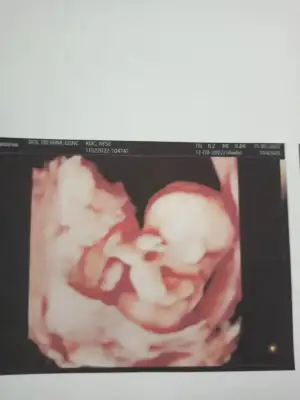

ozele gidiyorum aslında kizlarda 12. haftdada bende öğrenmiştim kesin konusmuslardi o zaman usg var ekliyorum yorumlarsanız sevinirim en azından kafam rahatlasin istiyorum ikilemde kalmak kötü hissediyor

Canım apış arası pek

görünmüyor sanırım dr da bu yuzden bekleyın demıs

Ben 15 haftalıkken gittigimde acıktı bacak arası gördük resmen

Ama 20 haftalık gittigimizde bacak arası kapalıydı dr bekleyın bıraz daha ayrıntılıda netleşir dedi

Yanı demem o ki pozısyonu uygun degılmiş demekki senin bebişinde

Umarım bı daha kı gottıgınde netleşir

Renkli usg ye doktor bisey demedi mi bacaklarını toplamış gibi tam anlaşılmıyor

bacak arası hep sim siyah renkli olanda da bulanık anlayamadık doktorda o yuzden emin olamadı. sanırım daha bekletmek istiyor biraz daha merak edin diyor 😀hayırlısı nasılsa oyle olsun inşallah sağlıkla hayırla dogsunlar bütün bebekler